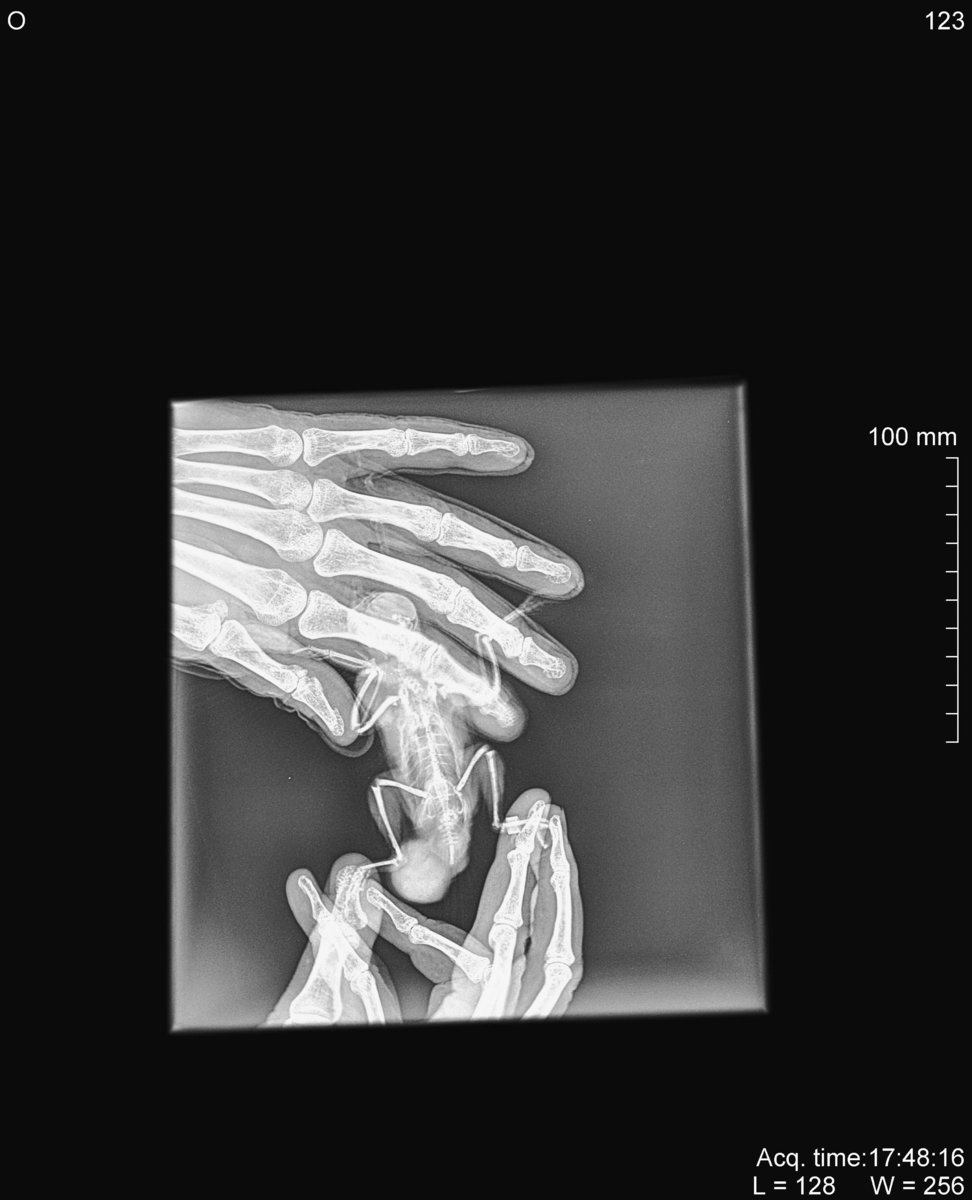

Рентген сделайте.

Рентген тоже сделали- выдали диск там куча файлов, пока не разобралась как их выложить сюда. Если кто подскажет, буду очень благодарна!

Если есть еще снимки других проекций -выкладывайте